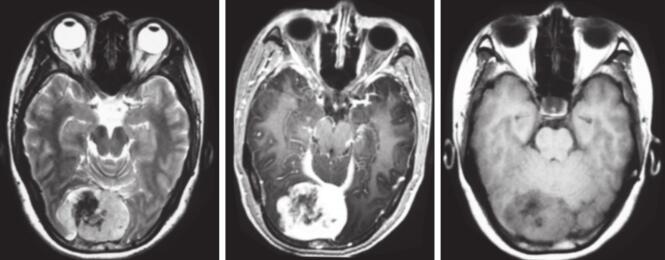

图2 术前头颅MRI和MRV检查图像

MRI提示窦汇区占位,T1、T2、DWI均表现为混杂信号,增强后可见明显不均匀强化,未见明显“脑膜拖尾征”。MRV提示窦汇不能显示,上矢状窦下端和两侧横窦均受压,部分显影